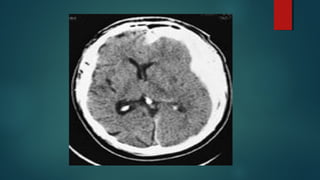

Este documento es el programa para un taller de imágenes del curso de emergencia 2015 impartido por el Dr. Víctor Delgado. El taller se centra en el uso de imágenes médicas para el diagnóstico y tratamiento de pacientes en coma traumático según la base de datos de Marshall. El Dr. Delgado es el único instructor repetido a lo largo del documento.